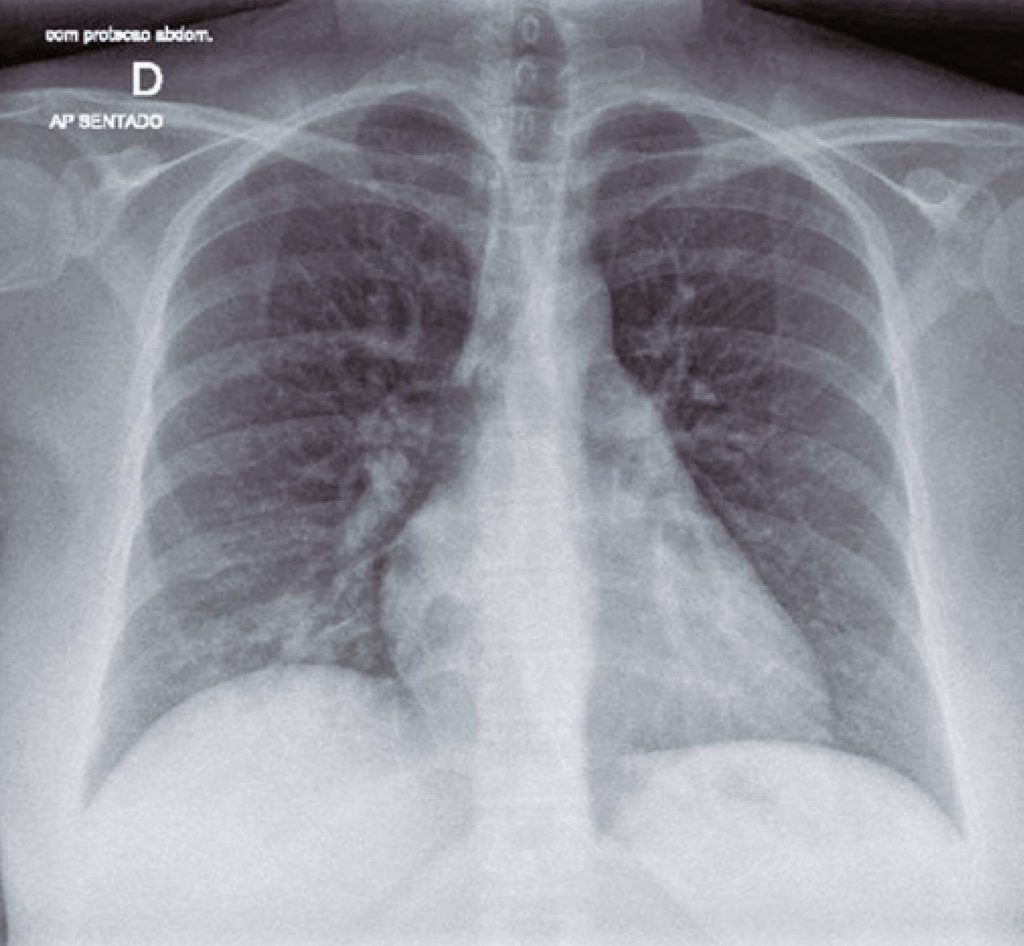

The coronavirus disease 19 (COVID-19) is responsible for the current worldwide pandemic. Treatment and prophylaxis are still under investigation. Convalescent plasma therapy could be an alternative. We report a case of a 41-year-old patient, at 28 weeks of gestation, was hospitalized with COVID-19. On the 10th day after onset of symptoms, the clinical picture worsened, and she required high-flow oxygen therapy (30L/minute), with 92% oxygen saturation, and chest X-ray showing mild bilateral opacities at lung bases. Blood tests showed D-dimer 1,004ng/mL, C-reactive protein 81mg/L, pro-calcitonin 0.05ng/mL and interleukine-6 42.9pg/mL. The therapy chosen was Tazocin® 12g/day, vancomycin 2g/day, and methylprednisolone 40mg/day. In addition, convalescent plasma therapy was administered (275mL) uneventfully, including SARS-CoV-2 antibodies and neutralizing antibodies >1:160. The patient had a fast recovery. The early administration of convalescent plasma, with high titers of neutralizing antibodies, may be an alternative option for severe COVID-19 during pregnancy, until further studies demonstrate an efficient and safe treatment or prophylaxis.